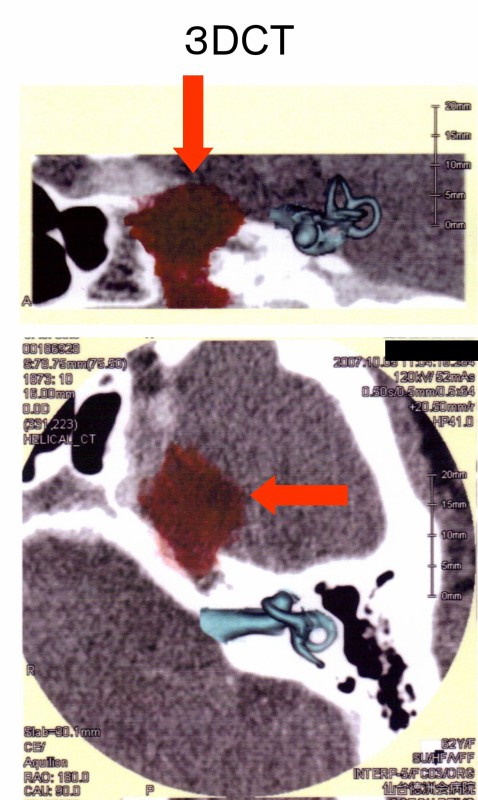

三叉神経領域についてMRI撮影(図4)を依頼したところ、左側三叉神経鞘腫が検出された。

眼振と腫瘍との関連に関して3次元CT(図5)を撮影したが、腫瘍の聴神経への進展は見られなかった。

図4

図5